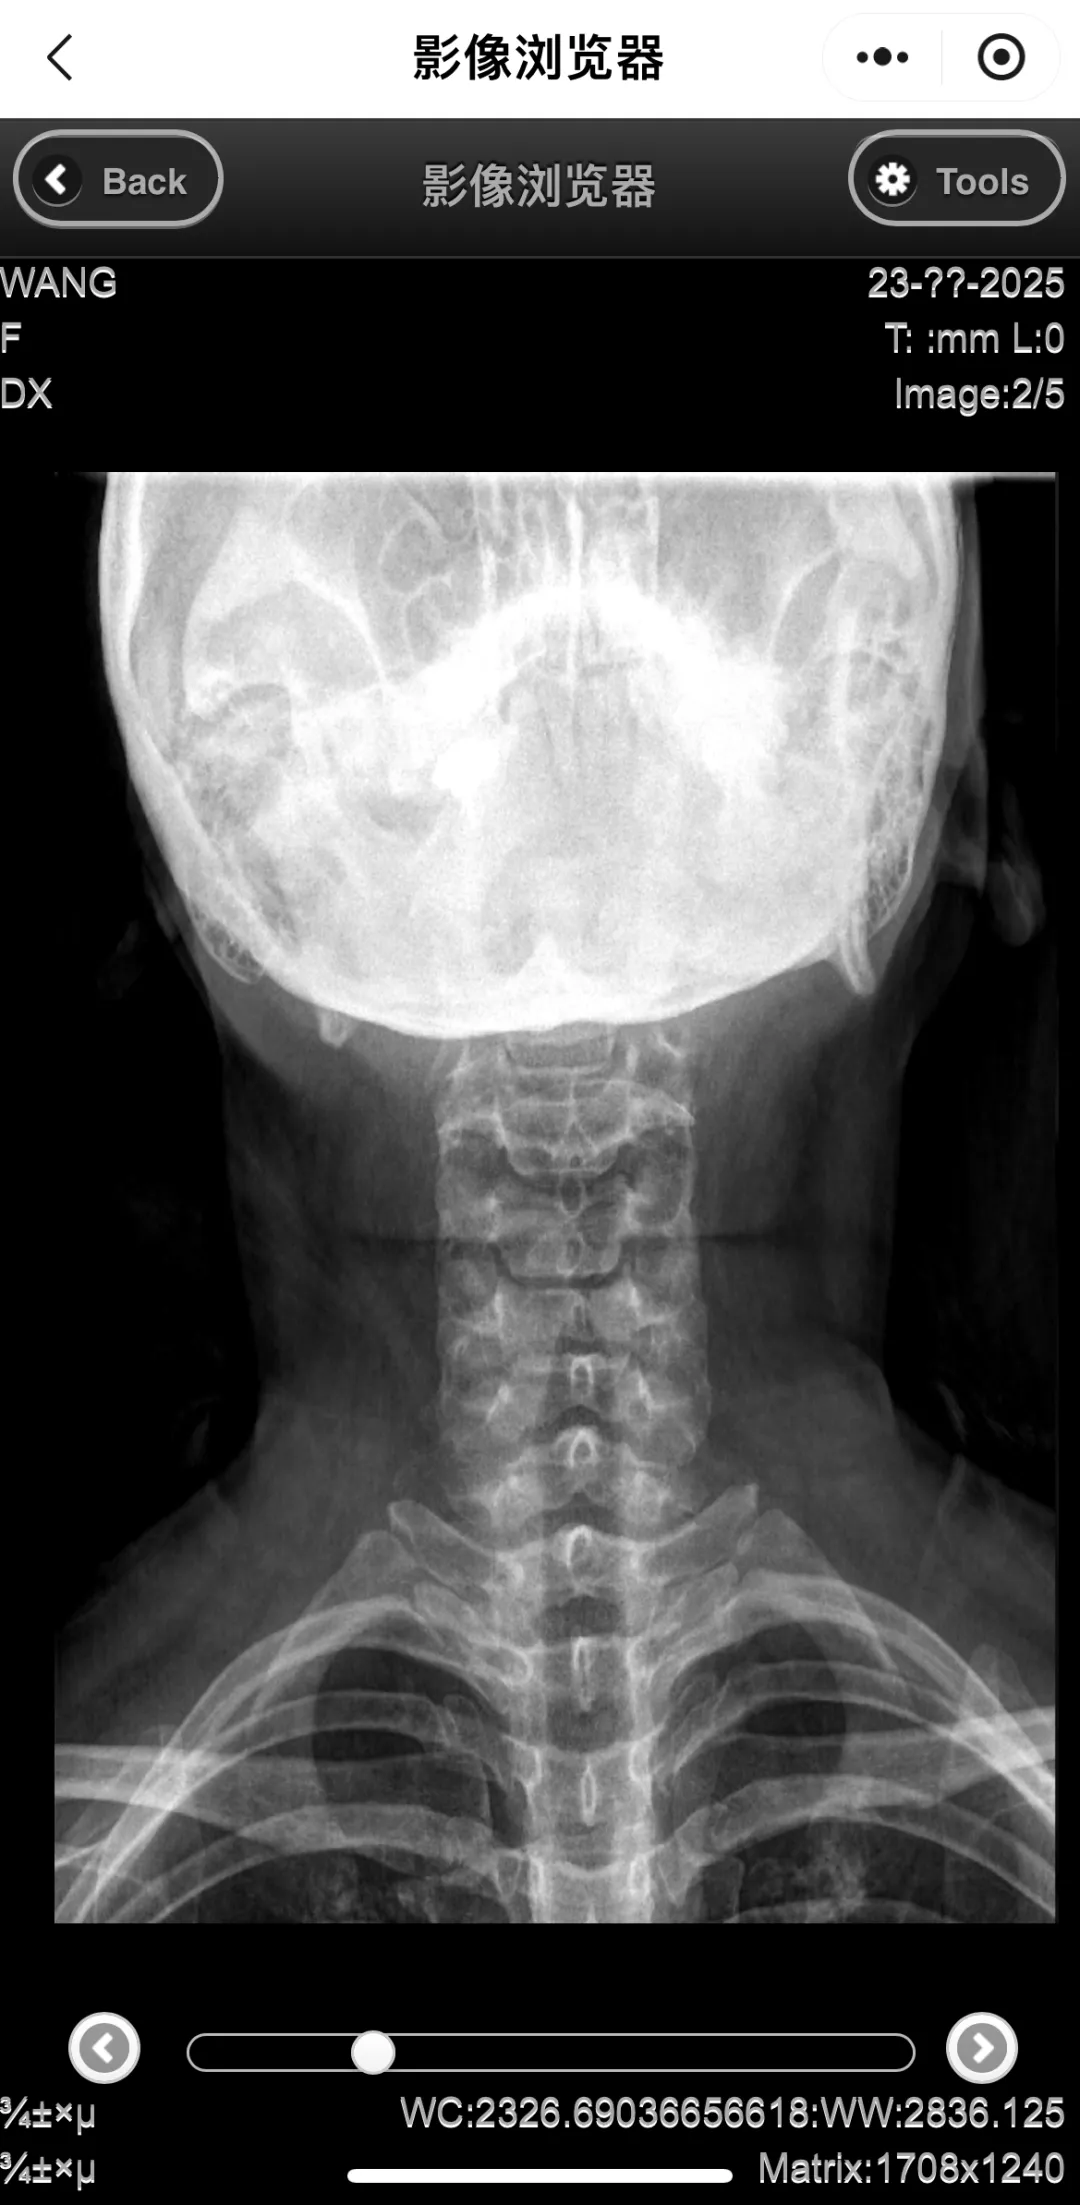

3.点击查看影像链接,进入“影像浏览器”界面,可直接查看胶片详情。如需要分享影像,可点击分享影像链接生成二维码。